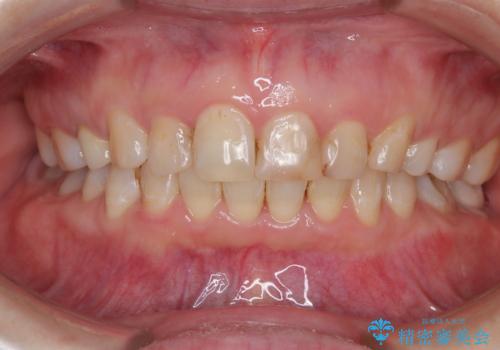

ハーフリンガル矯正|下顎前歯3本の特異症例を抜歯矯正で改善